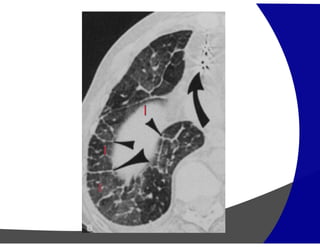

Faveolamento

Pneumonia intersticial Usual